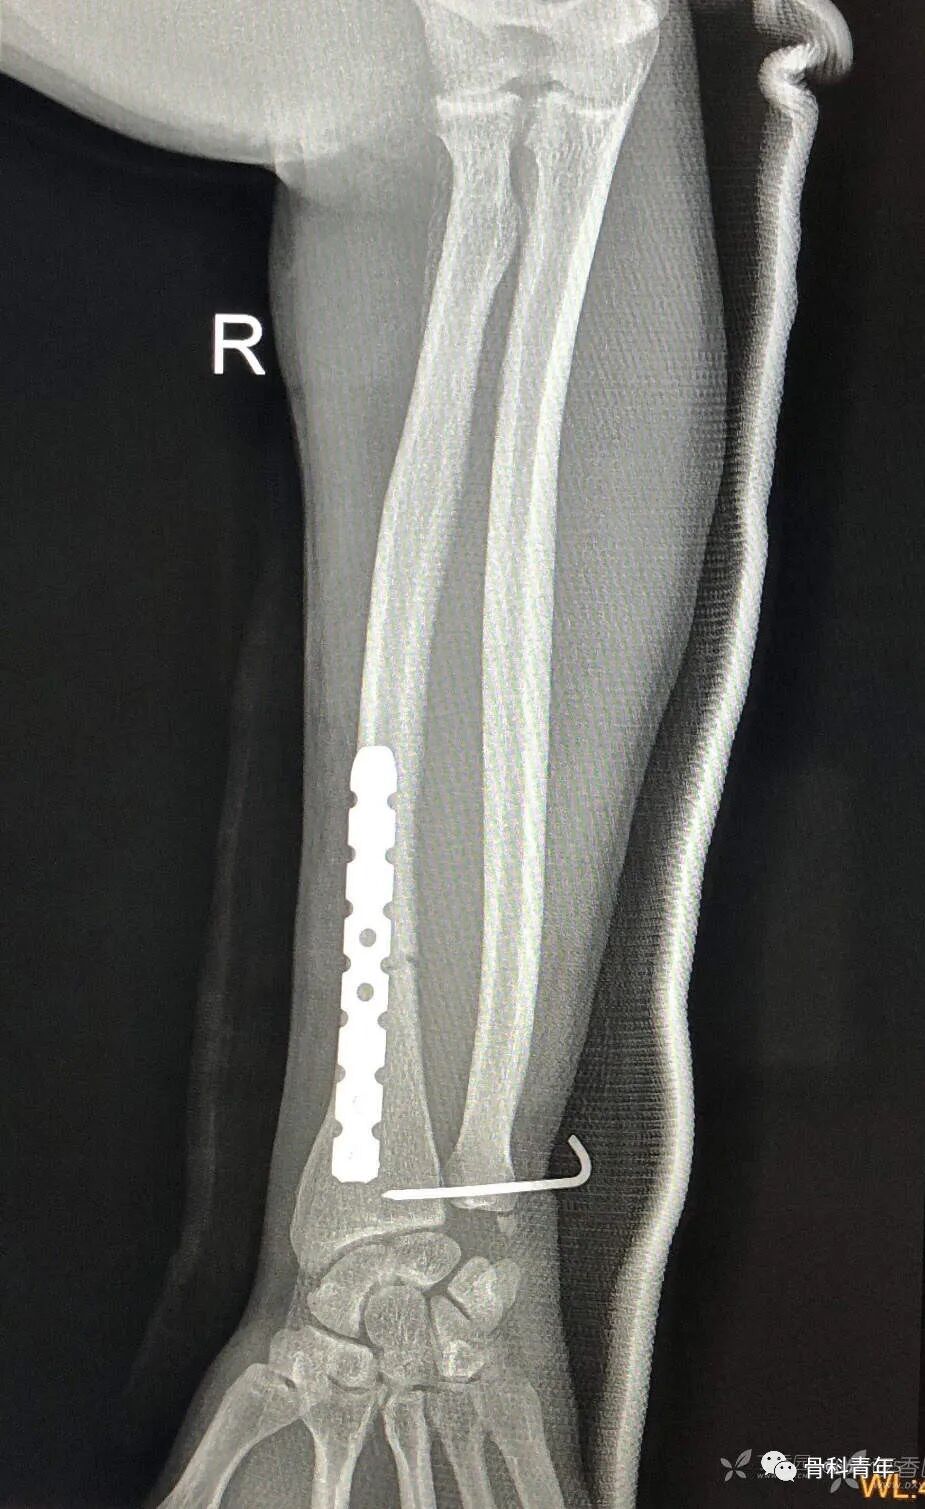

25.尺桡骨双骨折

26.盖氏骨折